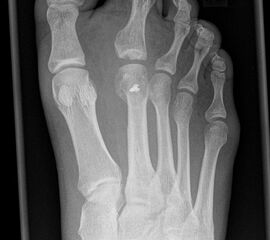

Besondere Bemerkungen zum Beispielbild:

• Verlaufskontrolle nach korrigierendem Vorfußeingriff bei Riesenwuchs des 2. Strahls mit verdicktem Os metatarsale II.

• Z.n. Amputation des Zehenendglieds D2.

• Z.n. Weil Osteotomie des Os metatarsale II.

• Hallux valgus interphalangeus.